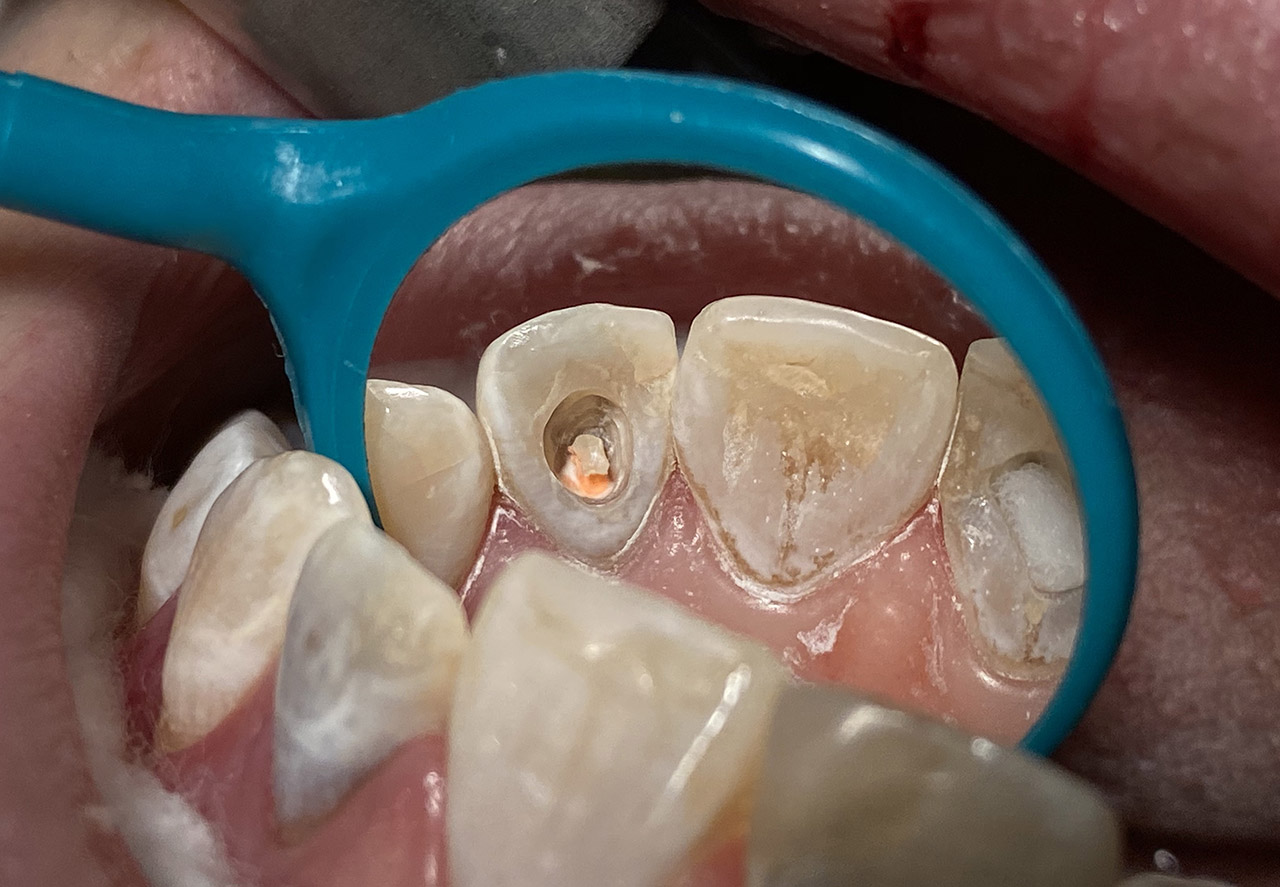

Traumatologie und Endodontie:

Nach Unfall/Sturz mittlerer Schneidezahn auf Gingivaniveau abgebrochen, Pulpa weit eröffnet, beide Nachbarzähne ebenfalls frakturiert.

Erstversorgung: Pulpektomie der Kronenpulpa, MTA, provisorischer Verschluß mit rosa Glasionomerfüllung.

Wiederaufbau der Nachbarzähne mit mitgebrachten (plus 1 Stein) Zahnstücken mit Kunststoff ergänzt und adhäsiv verklebt.

2. Schritt nach Aushärtung von MTA: Entfernung der Kronenpulpa im Bruchstück zur Vermeidung von Verfärbung, Füllung mit Kunststoff.

Adhäsives zementieren des abgebrochenen Zahnstücks.